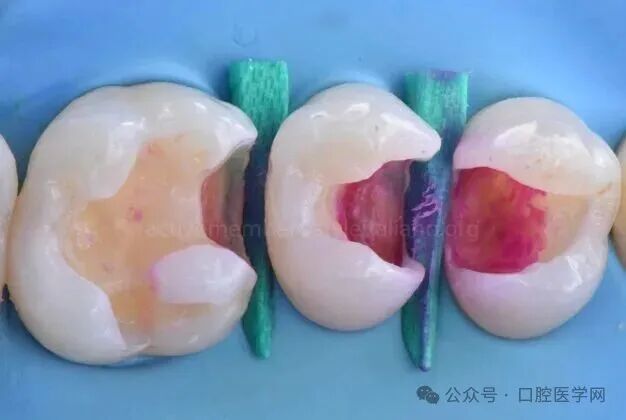

图3

龋坏去除前,放置2枚楔子以隔离并保护深龋颈缘。Ⅱ类洞存在极深龋损。

图4

初步龋坏去除后,感染牙本质区域仍清晰可见;因此使用龋损显色剂标记需进一步去除的区域。

图5

龋损显色剂标记出残留感染牙本质,需进一步去除。